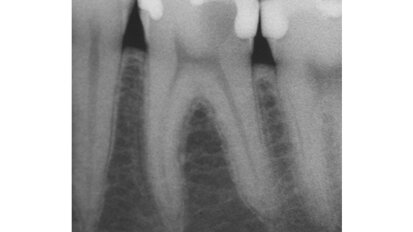

Hybridní terapie alignery